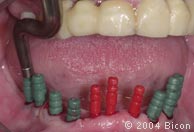

105. |

拆除临时义齿后隐肩基台的唇颊侧观。 |